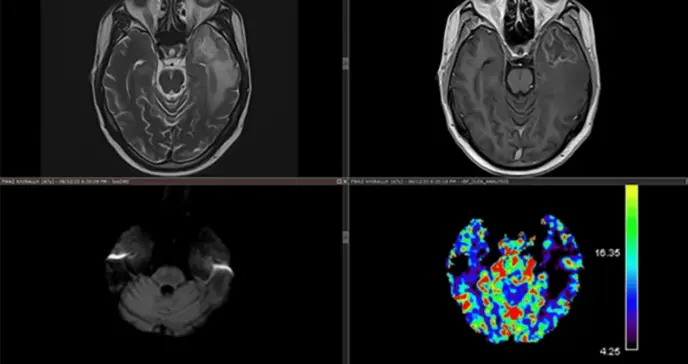

Una imagen de resonancia magnética del cerebro que muestra cuatro cuartos: el cuarto superior izquierdo es una imagen ponderada en T2, el cuarto superior derecho es una imagen ponderada en T1 con contraste, el cuarto inferior izquierdo es una imagen de resonancia magnética ponderada por difusión, el cuarto inferior derecho es una imagen ponderada por susceptibilidad.

La resonancia magnética cerebral con secuencias avanzadas mostró una lesión en lóbulo temporal izquierdo de 18x13 mm con características típicas de necrosis por radiación: hiperseñal en T2/FLAIR, realce anular en T1 con gadolinio, restricción en difusión y espectroscopia con elevación de lactato (2.3 ppm) y reducción de NAA (1.8 ppm). El estudio de perfusión no mostró hipervascularización, descartando recidiva tumoral. El EEG demostró actividad delta focal temporal izquierda sin descargas epileptiformes.